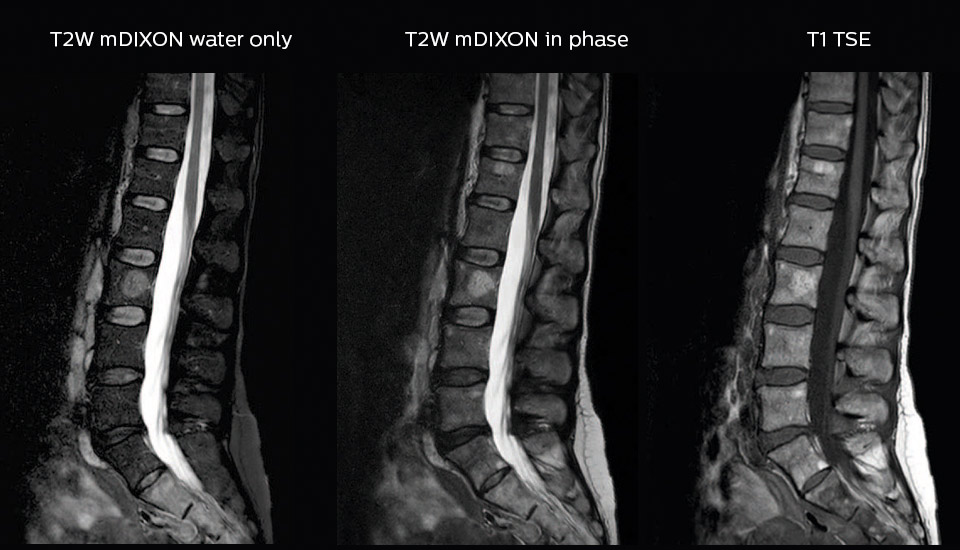

“In our lumbar spine MRI, the value of mDIXON TSE is so obvious. Normally we perform T1 and T2 scans in sagittal and transverse orientation.It used to take too much time to add a sagittal T2 with good fat suppression.But now, using mDIXON TSE, we get the sagittal T2 fat suppressed images ‘for free’, that is: without adding time.”

“Diagnostically that is a great benefit. I sometimes see abnormalities in the fat suppressed sagittal T2 that would be quite challenging to notice in the T2 without fat suppression. There have been several diagnoses that I could make easier because of our exam setup with mDIXON TSE, such as sacrum insufficiency fractures and sacroileitis; these were more challenging with our previous exam setup.”